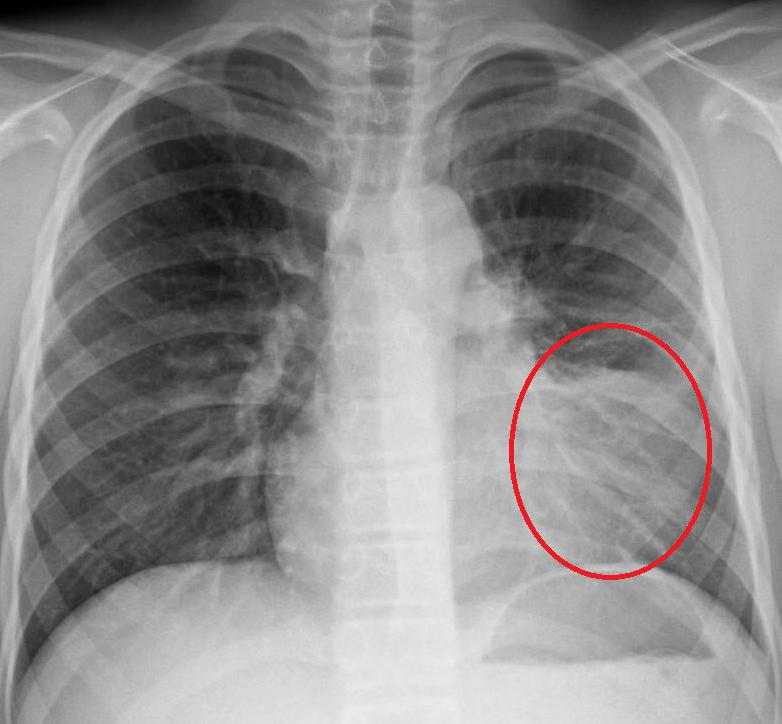

Как определить, что пневмония побеждена, если больной продолжает кашлять? Для этого необходимо сделать рентгеновский снимок легких. Иногда остаточные явления после пневмонии на рентгене наблюдаются как незначительные затемнения на легких. Их можно хорошо разглядеть на пленке.

Чтобы устранить воспалительный процесс в легких, назначается антибактериальная терапия. Процесс лечения легко контролировать с помощью рентгена. А вот бронхит как остаточное явление пневмонии на снимке можно не заметить. Это случается тогда, когда врач не имеет надлежащего опыта или рентгеновское оборудование низкого качества.

Можно увидеть остаточные явления после пневмонии на рентгене. Чтобы их не допустить, лечение антибактериальными препаратами должно продолжаться от 10 до 14 дней и никак не меньше. Кроме противовоспалительных средств, больной также должен принимать и отхаркивающие лекарства.

Но если кашель сильный и не проходит долгое время, то лучше всего обратиться за помощью к врачу. Специалист определит, насколько опасны остаточные явления пневмонии, на рентгене.

Обычно при подозрении на пневмонию, исходя из клинических и лабораторных данных, пациенту выполняют рентгенограмму в прямой и боковой проекции. Компьютерную томографию выполняют с целью выявления осложнений и для выбора дальнейшей тактики лечения.

Во многих случаях для постановки диагноза пневмония используют рентгенографию, но в некоторых случаях метода недостаточно в связи с меньшей информативностью в сравнении с компьютерной томограммой. КТ назначают в случаях, когда лечащего врача настораживает тот факт, что клинические симптомы у пациента при лечении не проходят, а наоборот происходит ухудшение общего состояния. Наиболее часто пневмонию приходится дифференцировать со злокачественными новообразованием и туберкулезом. Долевая пневмония на рентгенограмме выглядит, как долевое затемнение в легком. Также выглядит большинство аденокарцином (бронхоальвеолярная карцинома) легкого и лимфома легкого.

Так выглядит долевая пневмония (слева) и рак легкого (справа) на рентгенограмме. Для уточнения диагноза всегда и обязательным условиям является выполнению больному КТ.